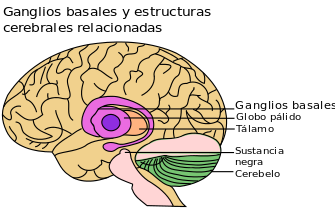

Los ganglios basales o núcleos basales ¿Qué son? ¿Qué papel desempeñan? Conjunto de masas de sustancia gris situadas dentro de cada hemisferio cerebral. Desempeñan un papel importante en el control de la postura y del movimiento.

Cuerpo estriado ¿Dónde se encuentra? ¿Qué divide en núcleos caudado y lenticular? ¿Cuál es su función? Está situado por fuera del tálamo. La cápsula interna (banda de fibras nerviosas) divide en núcleo caudado y núcleo lenticular. Su función está relacionada con el movimiento muscular.

Forma el principal lugar a partir del cual los estímulos de salida abandonan los núcleos basales. EL GLOBO PÁLIDO

SON LAS FIBRAS PALIDOFUGALES Asa lenticular -> núcleos talámicos Fascículo lenticular -> subtálamo Palidotegmentarias -> teg. cau. del mesencéfalo Palidosubtalámicas -> núcleos subtalámicos

Funciones de los ganglios basales... LA INFORMACIÓN SE INTEGRA DENTRO DEL. .... CUERPO ESTRIADO

Los núcleos basales tienen como función... Controlar movimientos musculares al influir en la corteza cerebral y ayudan en la regulación del movimiento voluntario y al aprendizaje de las habilidades motoras.